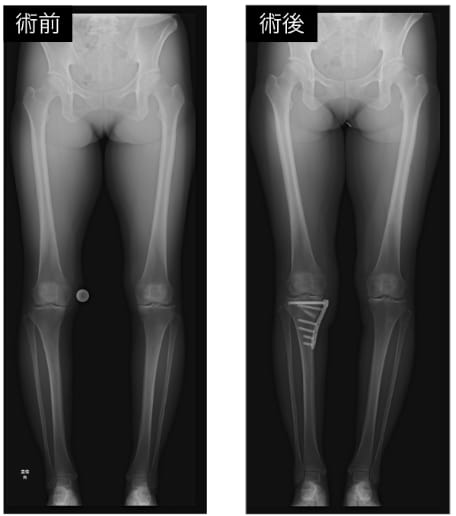

骨切り術は、寛骨臼形成不全を伴う変形性股関節症や変形性膝関節症、外傷後変形などにより、疼痛や機能障害を認める症例に対して行っています。骨を適切な角度で切り、関節の被覆やアライメントを矯正することで関節への負担を軽減し、疼痛の改善と関節機能の温存を図ることを目的としています。特に若年者や活動性の高い患者において、人工関節置換術を回避または延期する治療選択肢として重要です。当院では、股関節疾患に対して寛骨臼回転骨切り術を、膝関節疾患に対して高位脛骨骨切り術を主に行っており、術前に画像を用いて状態を詳しく評価し、患者ごとに適した治療を行っています。

寛骨臼形成不全に対する低侵襲寛骨臼回転骨切り術(SPO)

変形性膝関節症に対する高位脛骨骨切り術(HTO)